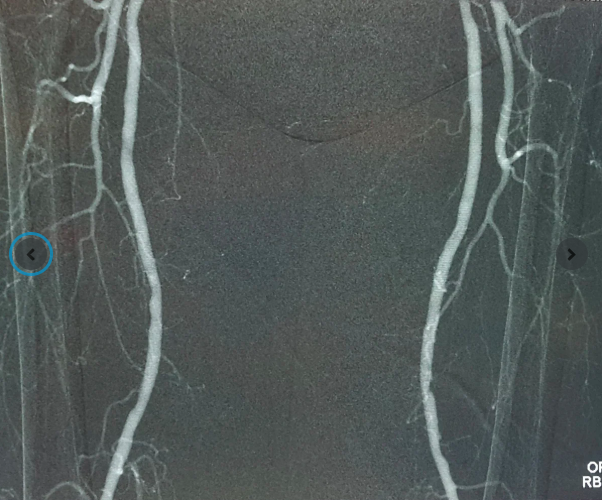

Kết quả siêu âm và chụp mạch tại FV cho thấy động mạch chậu phải bị tắc hoàn toàn đoạn dài, hẹp nặng động mạch chậu trái, động mạch chân phải bị tắc nghẽn hoàn toàn, động mạch chân trái tắc trên 90%. Máu từ tim gần như không xuống được hai chân. – lý do khiến ngón chân bị hoại tử và tình trạng đau nhức liên tục các ngón chân phải.

Với hệ thống Angiodroid, khí CO₂ tinh khiết được bơm vào mạch máu, thay thế thuốc cản quang truyền thống, vẫn cho hình ảnh X-quang sắc nét và đồng thời đảm bảo an toàn cho thận. Đây là công nghệ đang được nhiều trung tâm y tế tiên tiến trên thế giới ứng dụng, nay lần đầu có mặt tại Việt Nam.

Ca phẫu thuật can thiệp mạch cho ông Đ. diễn ra trong phòng Cathlab với sự hỗ trợ của máy chụp mạch bằng khí CO₂ Angiodroid, hệ thống DSA Philips Allura Xper và các dụng cụ cần thiết. Mục tiêu của phẫu thuật là khai thông dòng máu đến được vết thương ở ngón chân, giúp cải thiện tình trạng lành thương cho bệnh nhân.

Sau đó, do động mạch chậu bên phải của bệnh nhân tắc hẹp nặng và không thể thực hiện can thiệp mạch, bác sĩ Trung tiếp tục thực hiện một phẫu thuật Bypass, tạo cầu nối ngắn dẫn máu từ động mạch đùi trái sang đùi phải. Phần còn lại của các vị trí tắc và hẹp động mạch đùi, dưới gối ở cả hai chân cũng được bác sĩ Trung nong bóng, đặt stent qua vết chọc kim nhỏ.

Sau hơn 3 tiếng cho ca phẫu thuật hybrid (kết hợp can thiệp nội mạch và phẫu thuật Bypass), kết quả cho thấy máu từ tim đã được dẫn đến cả hai chân người bệnh, giúp cải thiện tình trạng tưới máu.